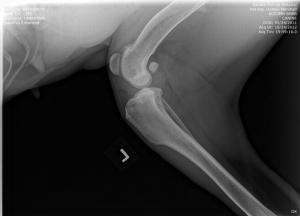

UPDATE: I know I have much to update in BHRR's Autumn's blog and before I go to bed in the wee hours; I shall update her blog plus add photos from her x-rays – taken of both legs, chest, back, legs, heart etc. on October 24th, 2012 and you can find them below! 🙂

From there, we are putting our creative hats on as she will need two cruciate surgeries – $6,000-$7,000+ – and the specialist is still looking at those eyes and what is going to be best….

She has three surgeries ahead of her – a spay and two separate cruciate surgeries and this is in addition to her almost $3,000 bills to date that have been racked up.